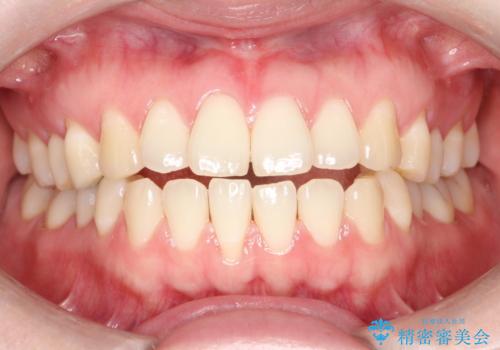

インビザラインによるガタつきの治療 クロスバイトの改善

- 中等度の叢生(ガタつき)のため、インビザラインによる非抜歯治療を計画します。